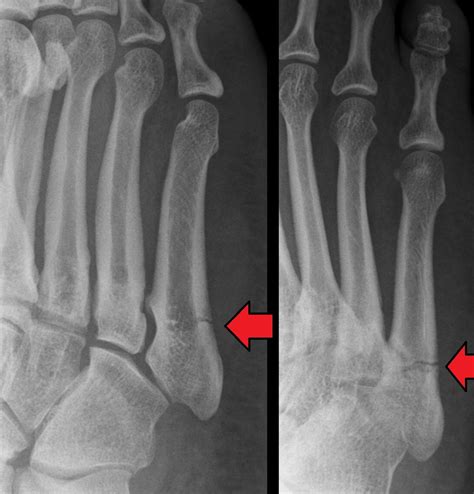

Often trauma to the pediatric metatarsals can be treated nonoperatively due to the remodeling potential of the bones and their tolerance of displacement, which typically results in good functional results.

Of fractures in the pediatric foot, metatarsal fractures are the most common. Peak incidence between 2nd and 5th decade of life. This is the complete home treatment guide for. Jones fractures occur in a small area of the fifth metatarsal that receives less blood and is therefore more prone to difficulties in healing. Learn vocabulary, terms and more with flashcards, games and other study tools. Fractures of the metatarsals are the most common fractures of the foot in children.19,24 in children under fractures of the phalanges in children are relatively rare. The cause is generally a. Each foot has five metatarsal bones, which are collectively referred to as the metatarsus, and none of them have individual names. It is important to give your child's foot time to heal completely, so. Well find out exactly how to get this bone feeling better! The first phalanx (great toe) is most frequently involved. Acute foot fractures of normal bones are usually caused by the dropping of heavy objects on the foot or by stress associated with abnormal repetitive trauma. However, as we become older the 'springiness' and padding of our feet tend to reduce. More frequently in children than many clinicians realize metatarsals (2nd and 3rd), calcaneus, fibula, and tibia are the 3 most common sites usually 1 bone only distal 1/3 of bone ex. Management of distal radius fractures programme. In older toe fractures also occur commonly in children. Are they treated like adults?